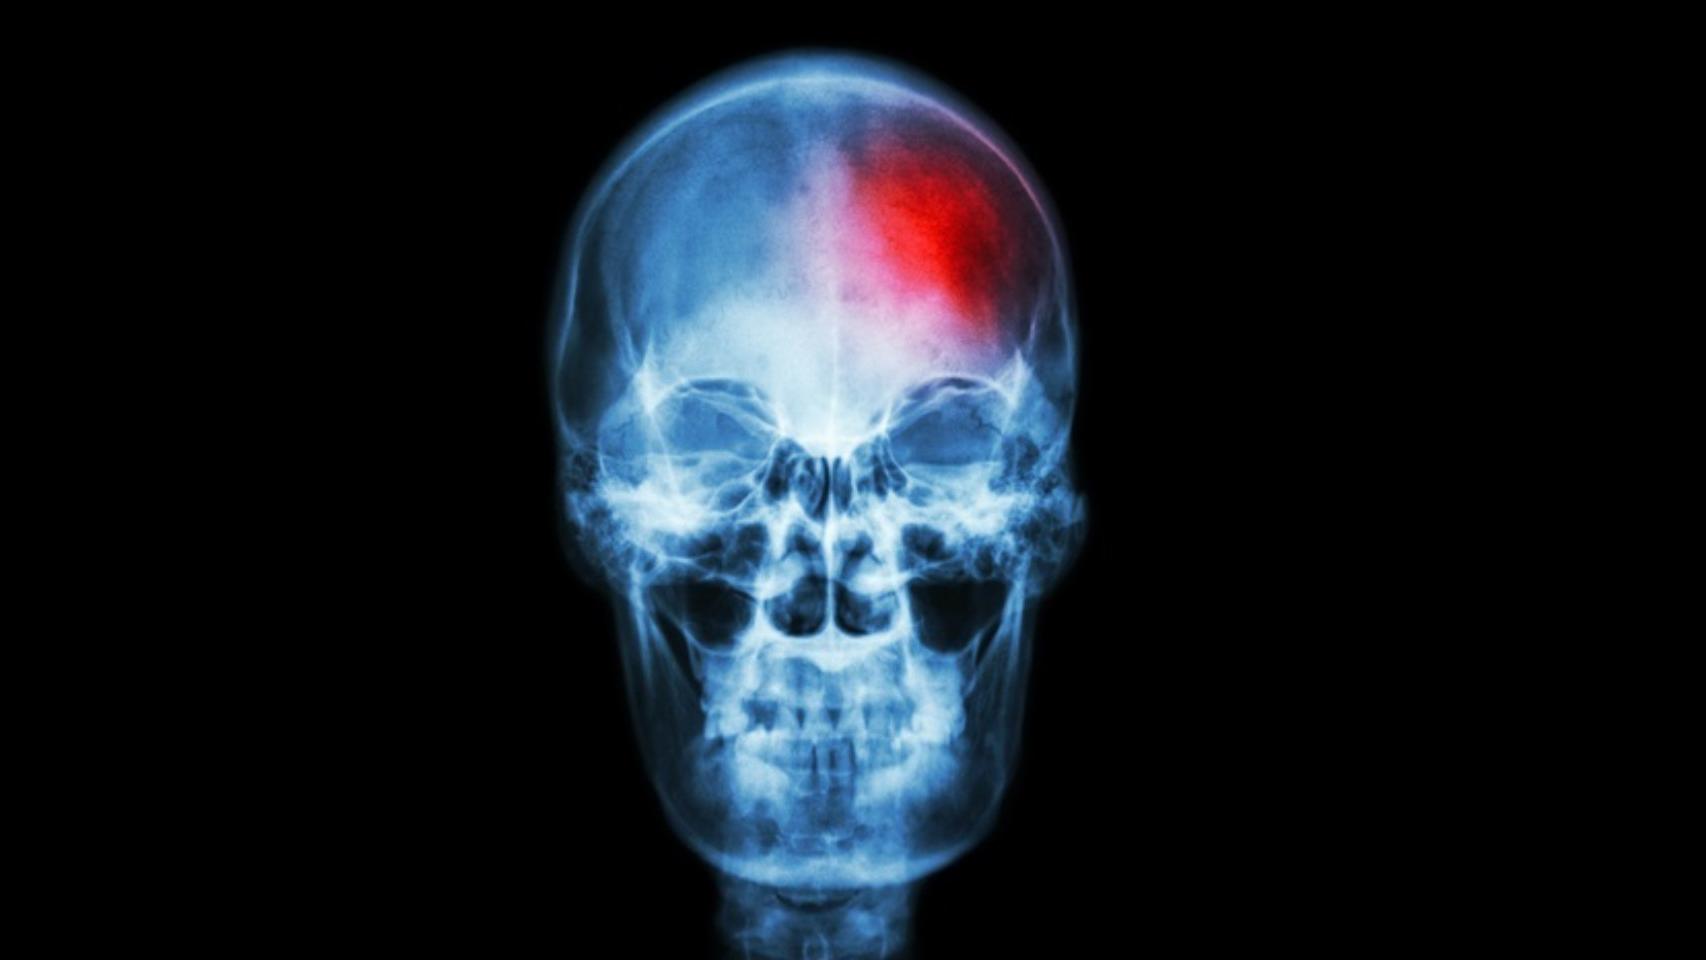

El infarto cerebral, también conocido como ictus, está creciendo como causa de muerte en todo el mundo. La Comisión de Neurología de la New World Stroke Organization, en colaboración con la prestigiosa revista The Lancet, ha proyectado que las muertes anuales por accidentes cerebrovasculares en todo el planeta aumentarán de 6,6 millones en 2020 a 9,7 millones en 2050. Mientras los países con un sistema sanitario más avanzado tienen medidas para contener esta sobremortalidad, serán los habitantes de países en vías de desarrollo quienes encajarán el golpe.

"El artículo posiciona al ictus como uno de los principales problemas de salud de nuestra sociedad", valora López-Cancio, como "segunda causa de muerte a nivel mundial y la segunda de discapacidad en adultos". Las consecuencias se traducen en costes directos de tratamiento y rehabilitación, e indirectos, en forma de pérdida de productividad. "Pero no solo para los propios enfermos, sino para las familias y la sociedad en general", recuerda. El ictus condiciona secuelas a largo plazo que implican una importante carga económica en cuidados, lo que repercute en las familias, y es una de las principales causas de depresión y demencia.